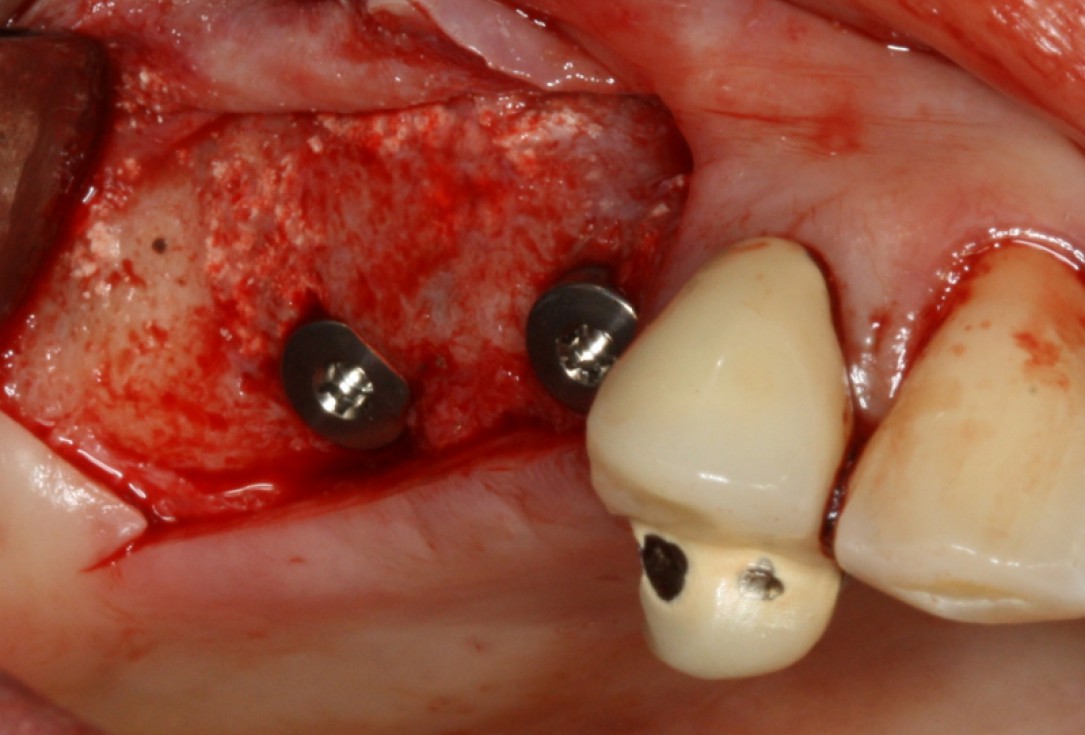

13/20 - Implant placementGBR with maxresorb® & Jason® membrane - Prof. Dr. Dr. D. Rothamel

17/20 - implant placementGBR with maxresorb® & Jason® membrane - Prof. Dr. Dr. D. Rothamel